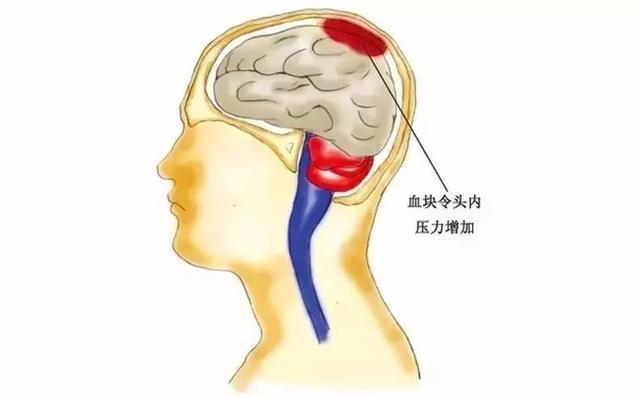

近幾年來,

腦溢血逐漸成為廣泛發生的急性病,

醫學上稱為

“出血性腦卒中”。

因為其發病快、病情凶險,

有時不能得到及時的治療,

因此成為病死率最高的疾病之一。